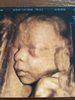

Moj przystojniak Oskar [emoji173][emoji173]

I fiutek na ostatnim zdjęciu [emoji7][emoji23]

1528969282629.jpg

1528969314660.jpg

1528969334089.jpg

1528969345451.jpg

Załączniki

• 1528969282629.jpg

461,4 KB · Wyświetleń: 452

• 1528969314660.jpg

593,8 KB · Wyświetleń: 440

• 1528969334089.jpg

554,2 KB · Wyświetleń: 436

• 1528969345451.jpg

761,4 KB · Wyświetleń: 455